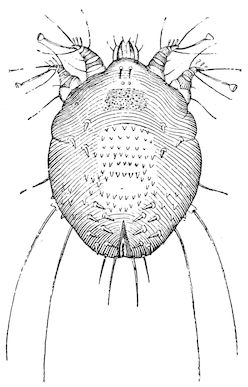

Fig. 1.—Rachitis in a young goat.